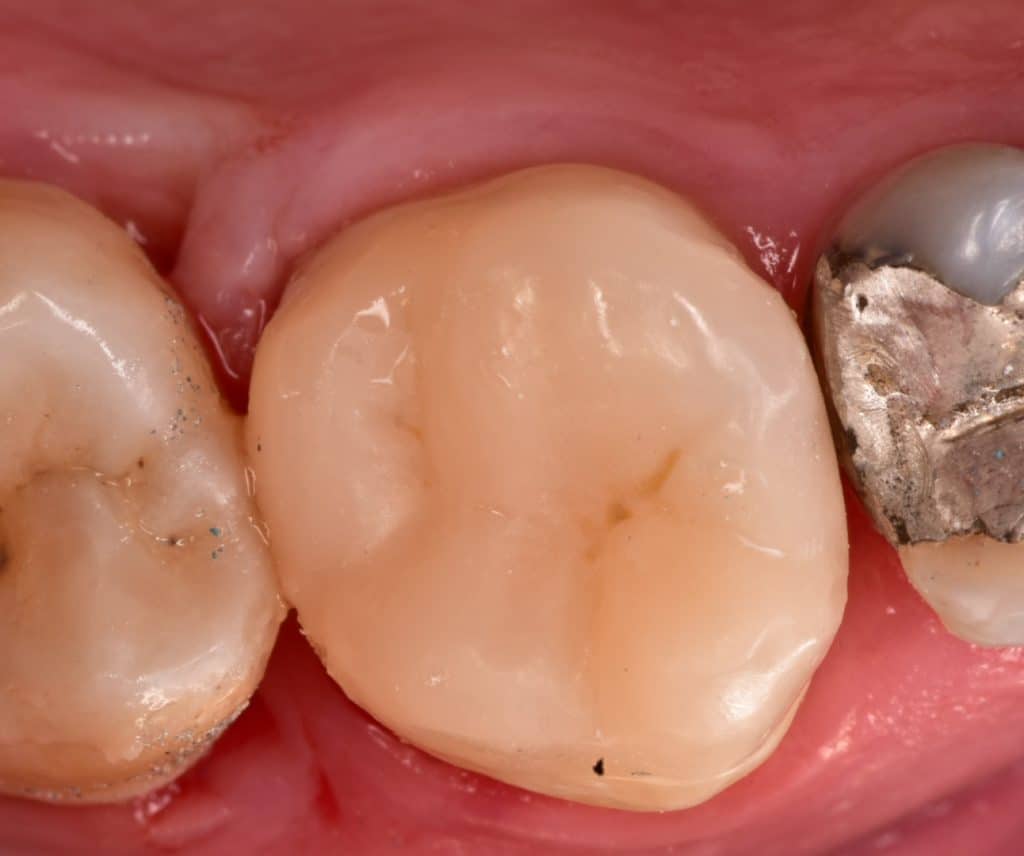

Initial situation, largely MOD cavity, endo_ treated tooth